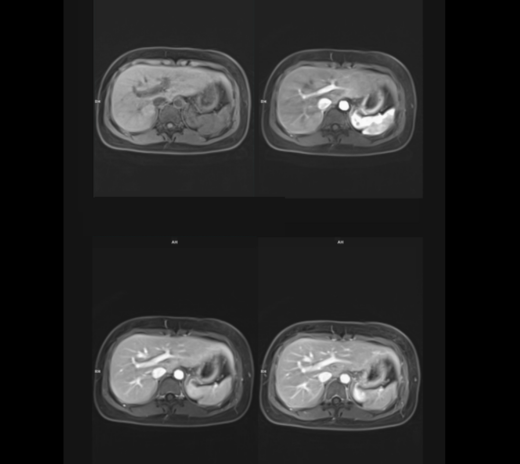

磁力共振扫描影像(自由呼吸的腹部)